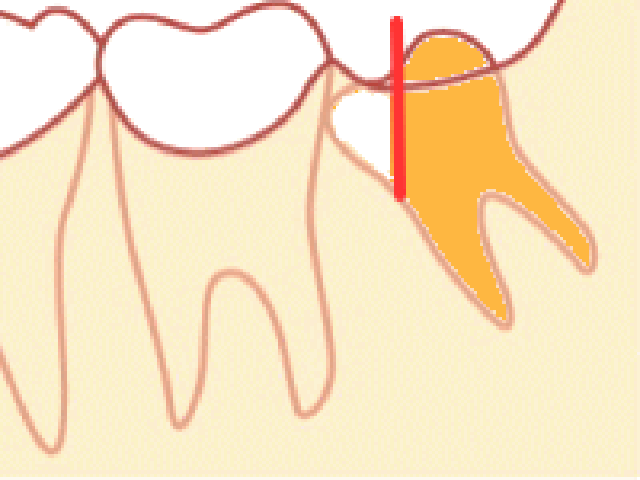

問題になることが最も多い、「斜め型」の親知らずを抜くための具体的な手順は次のようになります。

この程度の傾きであれば、骨は削らないで抜くことができます。

4.歯の頭を一部削ります

斜めになって前の歯にぶつかっている場合には、そのまま引っ張ってもぶつかって抜けません。そのため、抜くときにぶつからないように親知らずの歯の頭を削ります。傾きが大きいときは、この時点で歯の頭の部分を全て削ることもあります。

手前の歯にぶつかる部分をカットしてから抜く場合もございます。